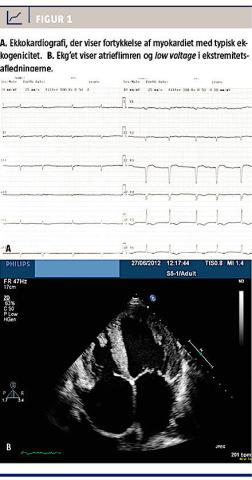

Ved den kliniske undersøgelse fandtes deklive ødemer med pitting, bilateral krepitation og svage respirationslyde på højre side. Et ekg viste low voltage i ekstremitetsafledningerne (Figur 1A), inverterede T-takker i V5-6 samt atrieflimren med en frekvens på 65 slag/minut. Ved en røntgenundersøgelse af thorax fandtes et stort højresidigt pleuraekssudat, hvorfor der blev foretaget pleuracentese; pleuravæsken var uden malignitetssuspekte celler. Ekkokardiografisk så man store atrier, fortykkelse af myokardiet (Figur 1B)med en glinsende karakter og tegn på diastolisk dysfunktion.

På ekg’et ses hyppigst low voltage i ekstremitetsafledningerne, pseudoiskæmi og forskellige former for arytmier, mens aflejringerne ekkokardiografisk giver et typisk billede af fortykket septum og bagvæg, granular sparkling og kompromitteret ventrikelfyldning. Størstedelen af patienterne får ved ekkokardiografi påvist kardiomyopati [3, 5]. Patienten i sygehistorien havde tydelige tegn på multiorgansvigt samt typiske ekg-forandringer og ekkokardiografiske forandringer. Symptomerne blev tidligere tilskrevet differentialdiagnosen sarkoidose. Man valgte at foretage biopsi fra det afficerede organ (myokardiet), hvorved AL-diagnosen blev bekræftet.